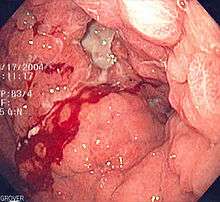

| A stomach ulcer that was diagnosed as cancer on biopsy and surgically removed. | |